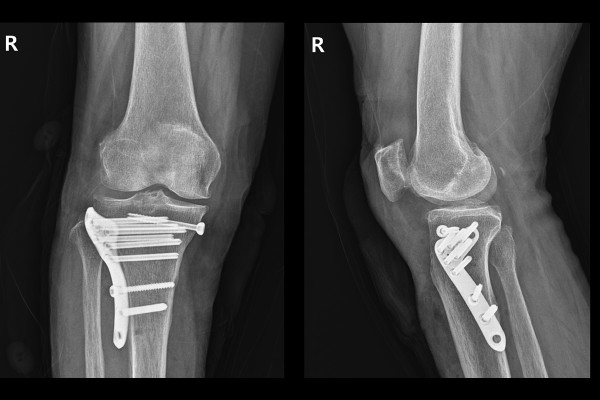

수술은 잘 마무리 되었고, 수술 후 X-RAY를 보면 골절되었던 무릎 경골 고평부가 강하게 잘 고정되었음이 확인됩니다.